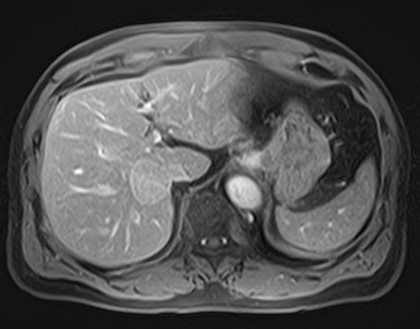

她這一年常覺得喘、右上腹隱隱脹脹,體重也掉了幾公斤。腹部超音波發現:

膽囊多發性結石

總膽管明顯擴張(約2.5公分)

醫師懷疑不只是結石那麼單純,轉至本中心做MRCP(磁振膽胰管攝影)。

影像顯示:整個總膽管呈現紡錘狀擴張,符合「先天性總膽管囊腫」(成人型,Type I)。這種情況在成人很少見,100個人裡大概只有10-20個會出現症狀,常見的是腹痛、黃疸,或反覆膽管發炎。更重要的是,這類囊腫長久下來,發生膽管癌的機率比一般人高10-20倍。林女士目前沒有急性發炎,目前先用藥物控制症狀,每6個月回來做一次核磁共振追蹤,暫時不需要開刀。她說:「現在知道是什麼問題,內心平靜多了。」